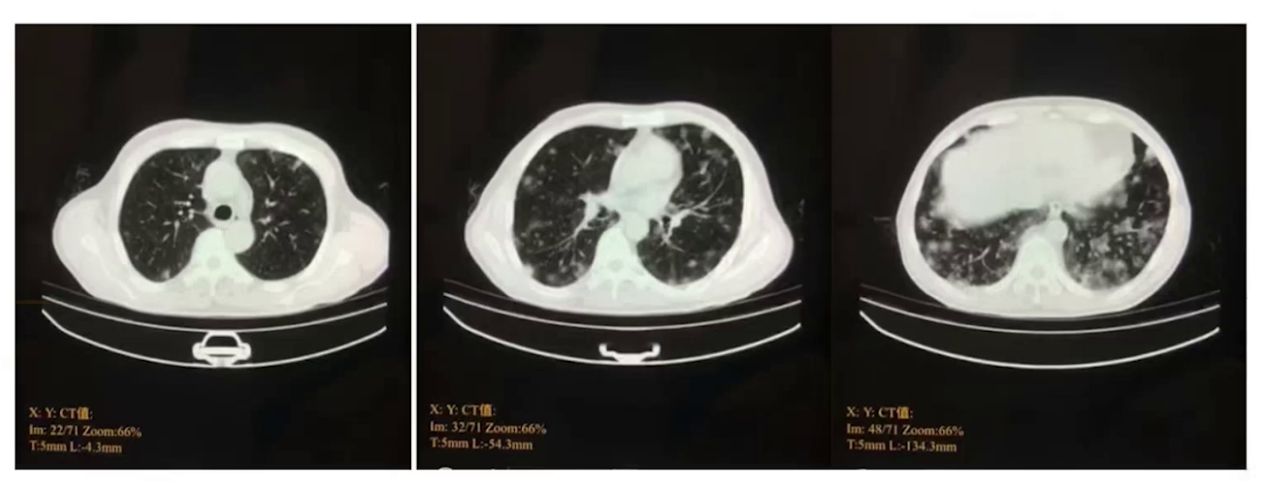

胸部CT(本院):两肺散在磨玻璃影。